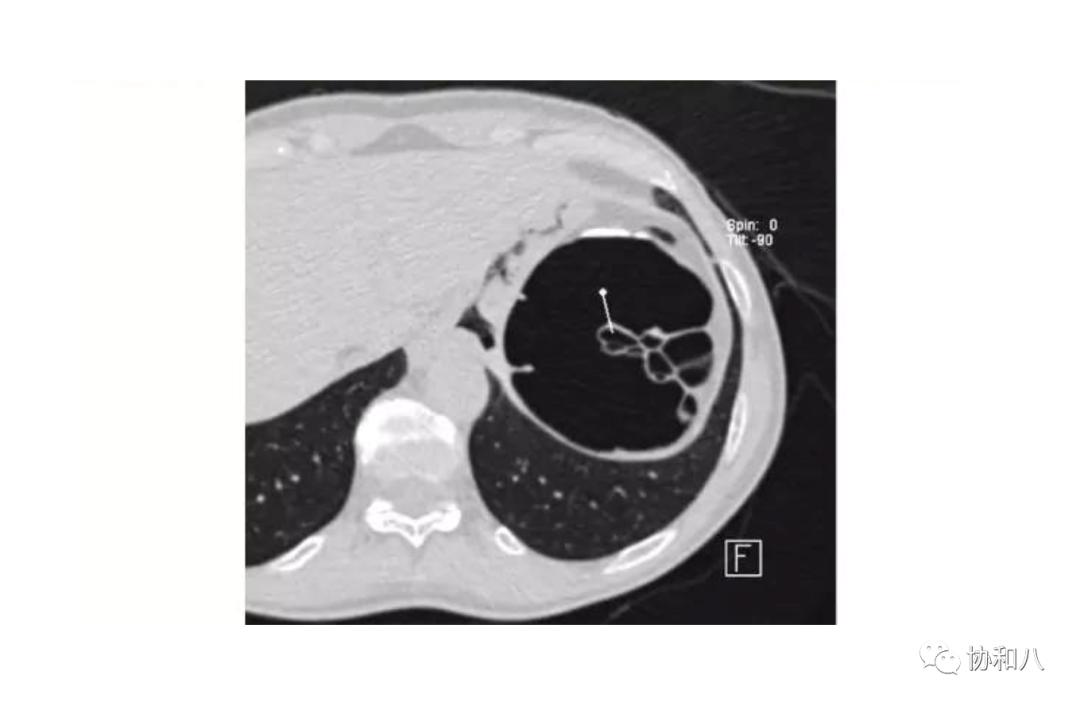

4. 葡萄串征:

常用于描述囊状支气管扩张(图1&2)的典型CT表现,也见于结肠含气囊肿(图3)。描述:簇状/串状囊腔呈葡萄串样。